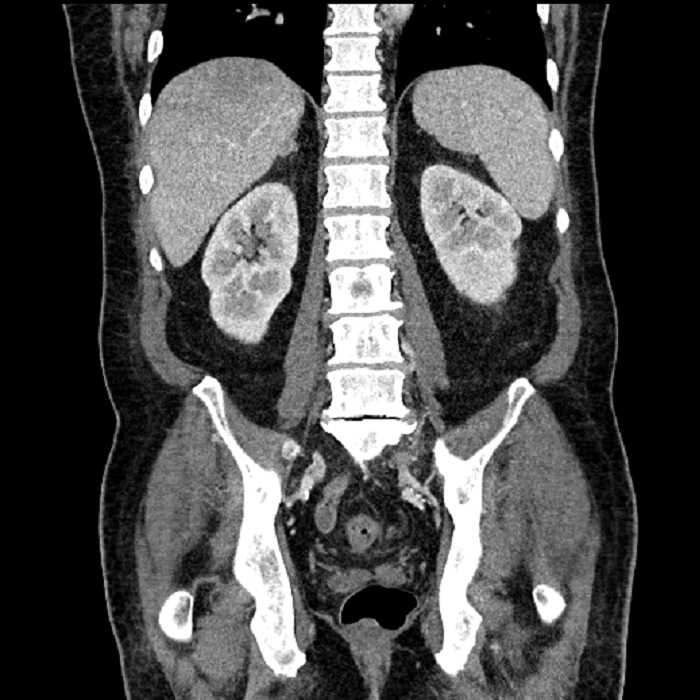

• Large fluid density structure in hepatic segments 7 and 8 measuring 10 x 7 x 7 cm with internal septation and circumferential ill-defined low density compatible with edema

• Peripherally enhancing subcapsular collections along the anterior margin of the left hepatic lobe measuring 3 x 1 cm and 2 x 1 cm

• Clearly marginated fluid density structure in segment 7 and several other scattered tiny hypodensities, which likely represent cysts

Acute sigmoid diverticulitis complicated by a small contained perforation and a large abscess in the right hepatic lobe. Additional small subcapsular abscesses along the anterior margin of the left hepatic lobe.

• The classic CT imaging appearance is a double target sign with internal low density surrounded by an internal enhancing rim (capsule) and a low density external rim (edema)

Hepatic abscess showing the double target sign with low density internally surrounded by a thin inner enhancing rim (red arrow) and ill-defined outer low density rim (yellow arrow). Blue arrow indicates an internal septation. Red arrows: additional smaller subcapsular abscesses. Red arrow: focal contained perforation associated with diverticulitis.